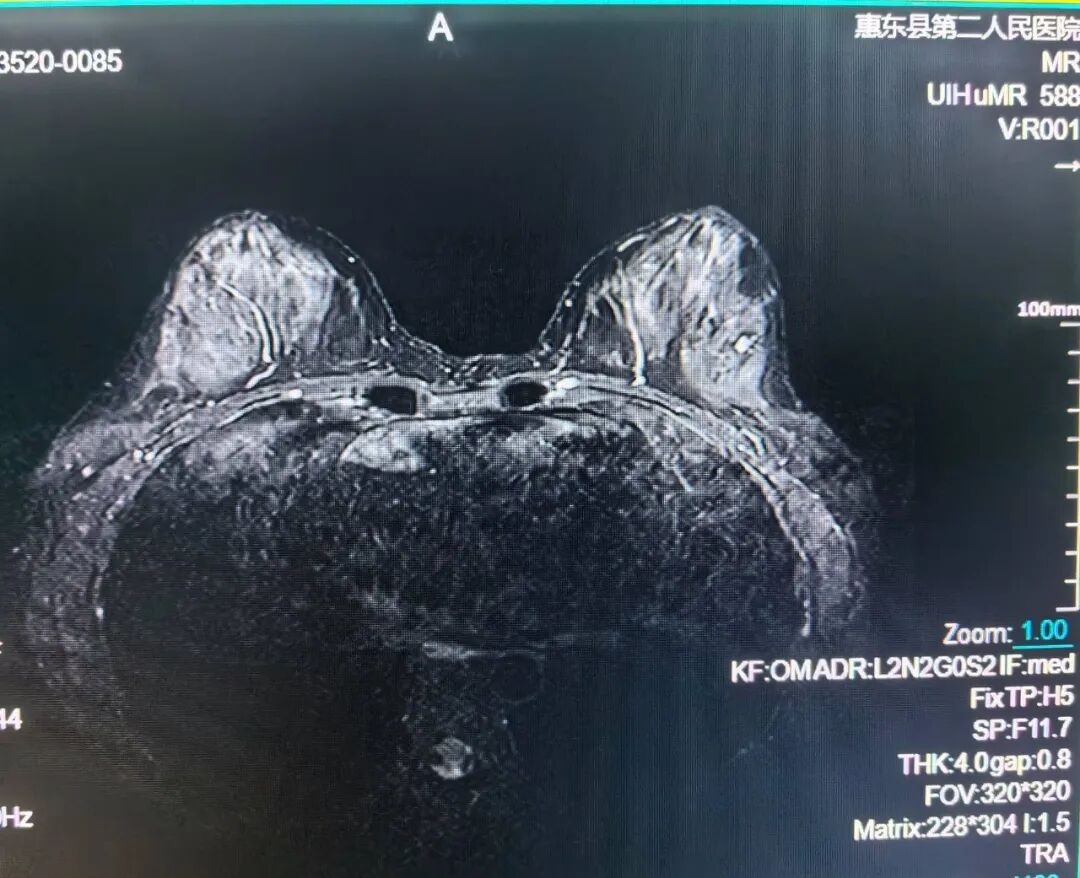

乳腺MRI检查

乳腺的良、恶性病变;高危人群乳腺癌筛查;新近诊断乳腺癌患者对侧乳腺的筛查等。